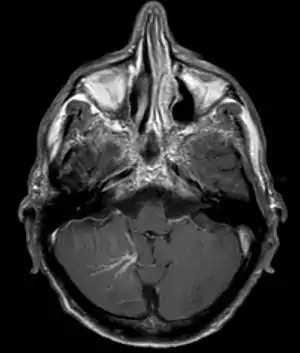

| Developmental venous anomaly in the cerebellum seen on axial contrast-enhanced T1 weighted MRI | |

DVA can be characterized by the caput medusae sign of veins, which drains into a larger vein. The drains will either drain into a dural venous sinus or into a deep ependymal vein. It appears to look like a palm tree.[1]